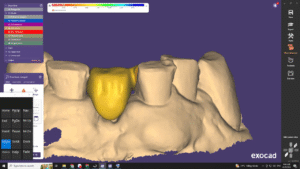

Scan răng kĩ thuật số

- Chẩn đoán và phát hiện bệnh lý răng toàn diện, lưu trữ hồ sơ bệnh án

- Hỗ trợ quy trình làm răng sứ, Implant, niềng răng kĩ thuật số, thiết kế nụ cười

- Đánh giá khớp cắn, lực nhai chính xác

- Kết hợp với AI cho ra nhiều lựa chọn điều trị khi niềng răng Invisalign